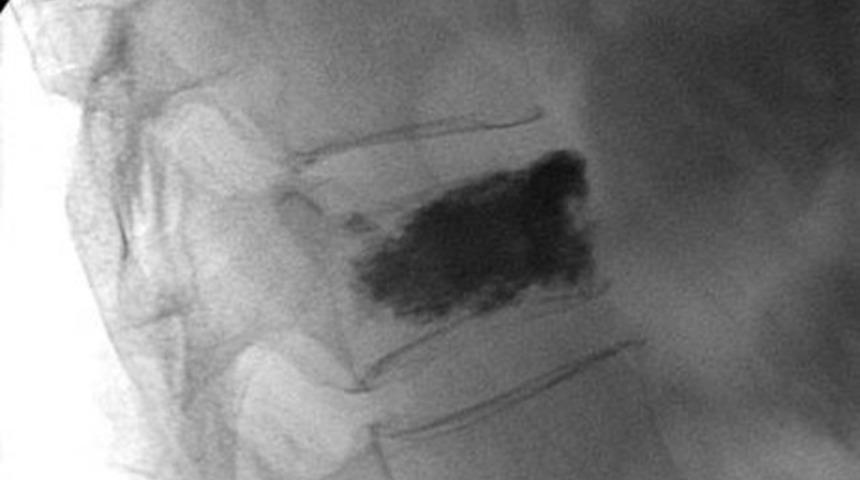

Vertebroplasti işlemi sırasında, lokal anestezi altında ve radyolojik kontrol ile, hasara uğramış olan omurga kemiği içerisine polimetilakrilat adlı kimyasal madde ( kemik çimentosu ) enjeksiyonu yapılır ve kemik sağlam hale getirilir.

Her iki işlem de genel anestezi uygulaması gerektiren işlemler değildir, lokal anestezi ve damardan uygulanan sakinleştirici ilaçlar yardımı ile yapılabilirler. Yüzüstü pozisyonda, hastanın kırığının bulunduğu seviye steril olacak şekilde temizlenir, fluoroskopi adını verdiğimiz özel bir görüntüleme sistemi ile kırık kemik görüntülenir. İşlem sırasında sürekli olarak radyolojik kontrol yapılır. Cildin kesilmesi gerekmez, sadece özel iğnenin geçebileceği kadar birkaç milimetre uzunluğunda bir cilt kesisi yeterlidir. Sürekli olarak radyolojik kontrol altında iğne kemiğin kırık bölgesine kadar uzatılır ve daha sonra iğnenin içinden kemik çimentosu enjekte edilir. İşlem yapılacak uygulamanın çeşidine göre, 15 dakika ile 30 dakika arasında sürer. Birkaç dakika içinde, enjekte edilen kemik çimentosu kemiğin içinde sertleşmeye başlar ve bir saat içinde tamamen donar.